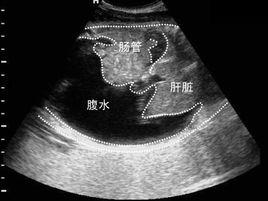

癌性胸腹水,也叫惡性胸腹腔積液,是中晚期癌症常見的併發症之一,也是部分患者的主要臨床症狀或體徵,嚴重的胸、腹水甚至可危及生命.外科治療手段如:抽水、放水等,有效地控制消除癌性胸、腹水對延長、拯救患者的生命有重要的現實意義。癌性胸腹水往往是血性的,內含大量紅白細胞。

①惡性胸水的疾病常見於肺癌、乳腺癌,其次為惡性淋巴瘤、卵巢癌、惡性胸膜間皮癌(多為血性積液)、食管癌、胃癌、賁門癌及病因不明的惡性腫瘤。常見症狀:呼吸困難、胸痛、胸悶、氣喘、咳嗽、血痰、體重下降、厭食、不適等,少數患者起初無症狀。②惡性腹水:引起癌性腹水的疾病:卵巢癌、肝癌、胃癌、胰。